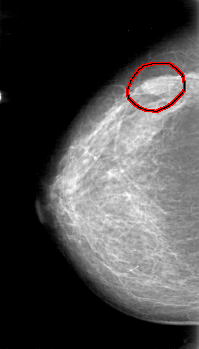

FILE: D_4046_1.RIGHT_MLO.OVERLAY

TOTAL_ABNORMALITIES 1

ABNORMALITY 1

LESION_TYPE MASS SHAPE OVAL MARGINS OBSCURED

ASSESSMENT 0

SUBTLETY 4

PATHOLOGY BENIGN

TOTAL_OUTLINES 1

BOUNDARY

RIGHT_MLO LINES 5281 PIXELS_PER_LINE 3106 BITS_PER_PIXEL 12 RESOLUTION 43.5 OVERLAY